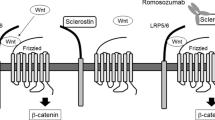

In 2001 two groups independently identified mutations in a new, rather small gene named SOST located on chromosome 17q12-21 that encodes for the protein sclerostin [58, 59]. At least 8 different mutations of the SOST gene have been reported leading to loss-of-function of sclerostin. Sclerostin is a glycoprotein with a cystine knot and three loops that is synthesized in the skeleton exclusively by mature osteocytes and inhibits bone formation at the bone surface by antagonizing the Wnt signaling pathway [60, 61]. Sclerostin binds to the first propeller of the LRP5/6 receptor and disables the formation of the co-receptor complex between LRP5/6 and the frizzled receptor. The action of sclerostin on the Wnt signaling pathway is facilitated by LRP4 [62, 63]. SOST mRNA is expressed in many tissues, especially during embryogenesis, but sclerostin is expressed postnatally only in terminally differentiated cells embedded within a mineralized matrix (osteocytes, mineralized chrondocytes and cementocytes). Consistent with this restricted expression of sclerostin, patients with sclerosteosis have no renal or cardiovascular abnormalities. Sclerostin in addition to its action on bone formation, stimulates the production of RANKL from neighboring osteocytes and increases bone resorption [64–66]. The production of sclerostin is regulated by different factors the most important being mechanical loading, PTH and estrogens, all of which reduce the production of sclerostin by osteocytes (Fig. 4) [67]. As expected, sclerostin was not expressed in bone biopsies from patients with sclerosteosis.

Schematic representation of sclerostin actions. Osteocyte-produced sclerostin inhibits the proliferation, differentiation and survival of osteoblasts and reduces bone formation; it stimulates also the production of RANKL by neighboring osteocytes and bone resorption. In osteoblasts, sclerostin binds to LRP5/6 and inhibits the Wnt signaling pathway, an action facilitated by LRP4. Production of sclerostin is decreased by mechanical loading, PTH, estrogens and other factors (from [67])